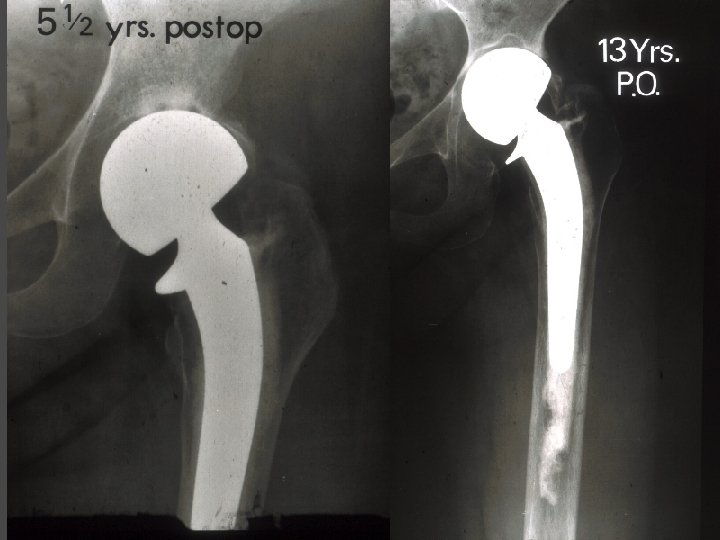

OSTEONECROSIS Cemented THA Results Yr No F-up Stauffer 82 Failure 10 yrs 8 yrs 50% Salvati 86 28 37% Kantor 96 28 7. 7 yrs 12. 5% Garino 97 123 6. 6 yrs 8%

OSTEONECROSIS Uncemented THA Results Yr Type No F-up Stem Socket (yrs) failure (%) Brinker 94 H-G 81 5 19. 7 6. 2 Lins 93 PCA 37 5 18. 9 2. 7 Piston 94 AML 35 7. 5 2. 9 5. 7 D’Antonio 97 HA-Omnifit 53 6 0 15